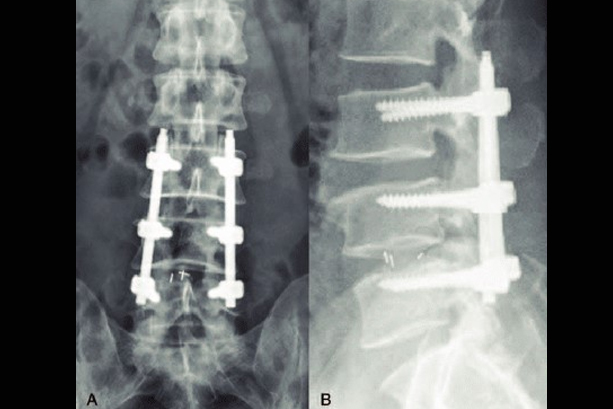

SRF TAKES PRIDE IN PRESENTING TO YOU A FEW INTERESTING CASES

More than 300 Underprivileged Patients have been Operated through our Foundation over the last 15 years !

Cases